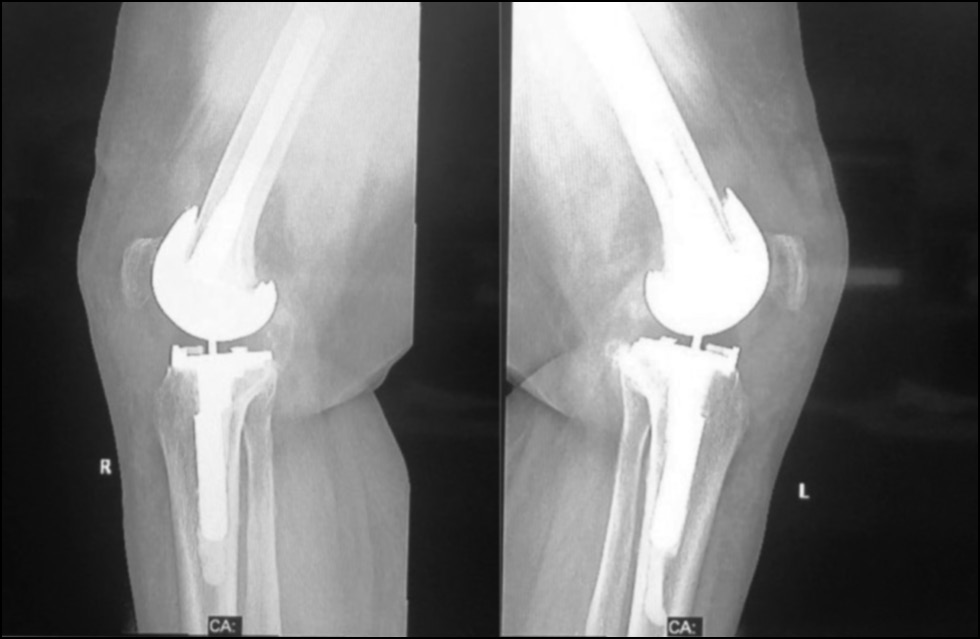

CASE 4. PATIENT 25

Age: 65 years.

Sex: Male.

Diagnosis: Bilateral advanced knee osteoarthritis.

Procedure: Bilateral simultaneous knee arthroplasty.

Associated illnesses: No associated comorbidities.

Postoperative follow-up: No postoperative complications were encountered.

Length of hospital stay: 6 days.

Radiological assessment (Fig. 23–26)

Fig. 24. Lateral preoperative x-ray right and left knees showing osteoarthritis.

Рис. 24. Предоперационная боковая рентгенограмма правого и левого колена с признаками остеоартрита.

Fig. 25. Ap postoperative x-ray showing bilateral total knee arthroplasty.

Рис. 25. Послеоперационная рентгенограмма с двусторонней тотальной артропластикой коленного сустава.

Fig. 26. Lateral postoperative x-ray right and left knees showing bilateral total knee arthroplasty.

Рис. 26. Послеоперационная боковая рентгенограмма правого и левого колена, демонстрирующая двустороннюю тотальную артропластику коленного сустава.